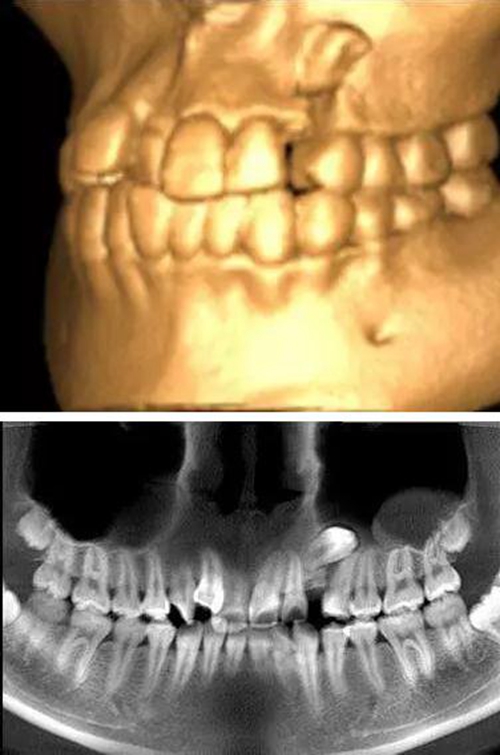

本案:患兒,女,14歲,因牙齒矯正來院,檢查見83滯留,43未見萌出,拍片發(fā)現(xiàn):43埋伏阻生于31、41、42根尖下方,按照正畸診療計劃,擬行43拔除術(shù)。

全景片

CBCT顯示